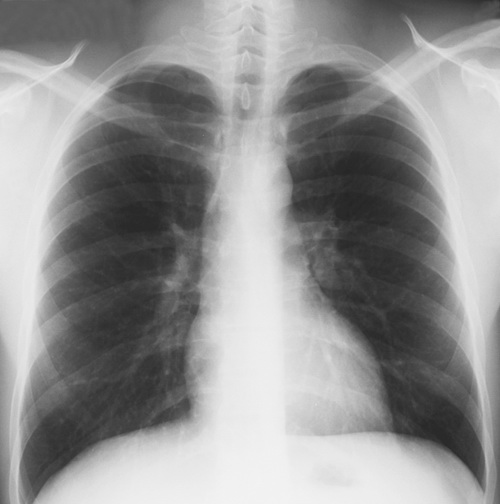

Mellkasfelvétel: általános, illetve munka alkalmassági kivizsgálás részeként, kardiológiai panaszok esetén, egyéb mellkasi panaszok hátterében lévő eltérések diagnosztizálásához, tumoros megbetegedések mellkasi áttétének kizárására használjuk.